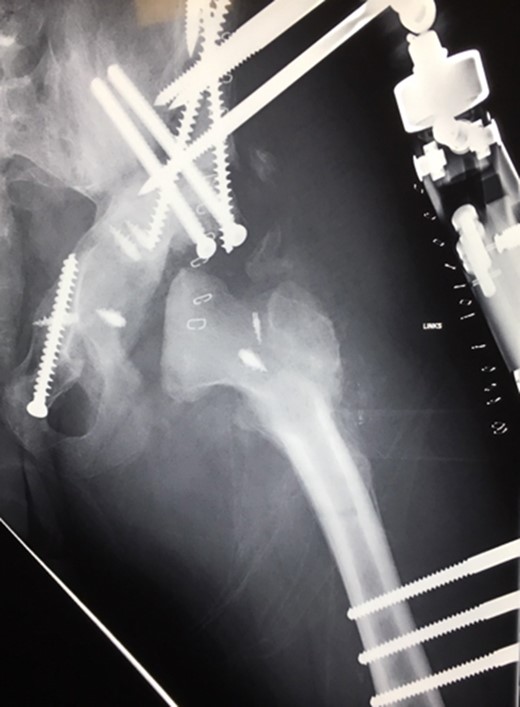

Ten years ago, a 12-year-old male presented to our clinic complaining about limping and massive swelling of the left hip. Figure 1 shows the initial X-ray and the 3D reconstruction of the left hip at first presentation when the femoral head, had already destroyed the lateral edge of the acetabulum like a mortar. Severe pain episodes have apparently not been noticed and a former hip dysplasia was not known. A brief clinical history revealed that the patient presented repeated episodes of finger biting and fevers from 2 to 8 years old. The intelligence level of the patient was at an average. The patient was admitted to a paediatric neurologist and a genetic test. A mutation of the NTRK1 gene was found and the diagnosis of CIPA was established. The right hip initially appeared to be normal and the patient was walking, therefore surgical reconstruction for the left hip was proposed due to massive swelling, inability of normal walking and significant limb length discrepancy. A Tönnis/Kalchschmidt triple pelvic osteotomy with open reduction and a shortening varus derotation osteotomy (VDRO) of the femur was performed (Fig. 2A–B). After 3 months the patient was walking again but another 3 months later the hip dislocated again without severe pain. Although the femoral head was already damaged the hip joint was reconstructed again by open reduction, capsular reconstruction with suture anchors and a trevira tube and a movable external fixator was used to temporary stabilize the joint (Fig. 3). The right hip at this time was still intact and was protected with a pneumatic orthotic device. A few months later in 2009, despite all surgeries, the left hip had entirely lost congruency and the right hip developed subluxation despite conservative treatment (Fig. 4). The patient was still walking so the decision to reconstruct the right hip with open reduction, capsular augmentation with a trevira tube, a triple pelvic osteotomy and VDRO was made (Fig. 5). Few months later this reconstruction failed as well and the hip dislocated without severe pain (Fig. 6).

(2008) Despite reconstruction the femoral head subluxated and rapidly lost congruency. An open reduction and capsular reconstruction with trevira tube, removal of the femoral plate and temporary fixation with an external fixator with movable hip mechanism for flexion of the joint (Orthofix MonoRail) was performed.